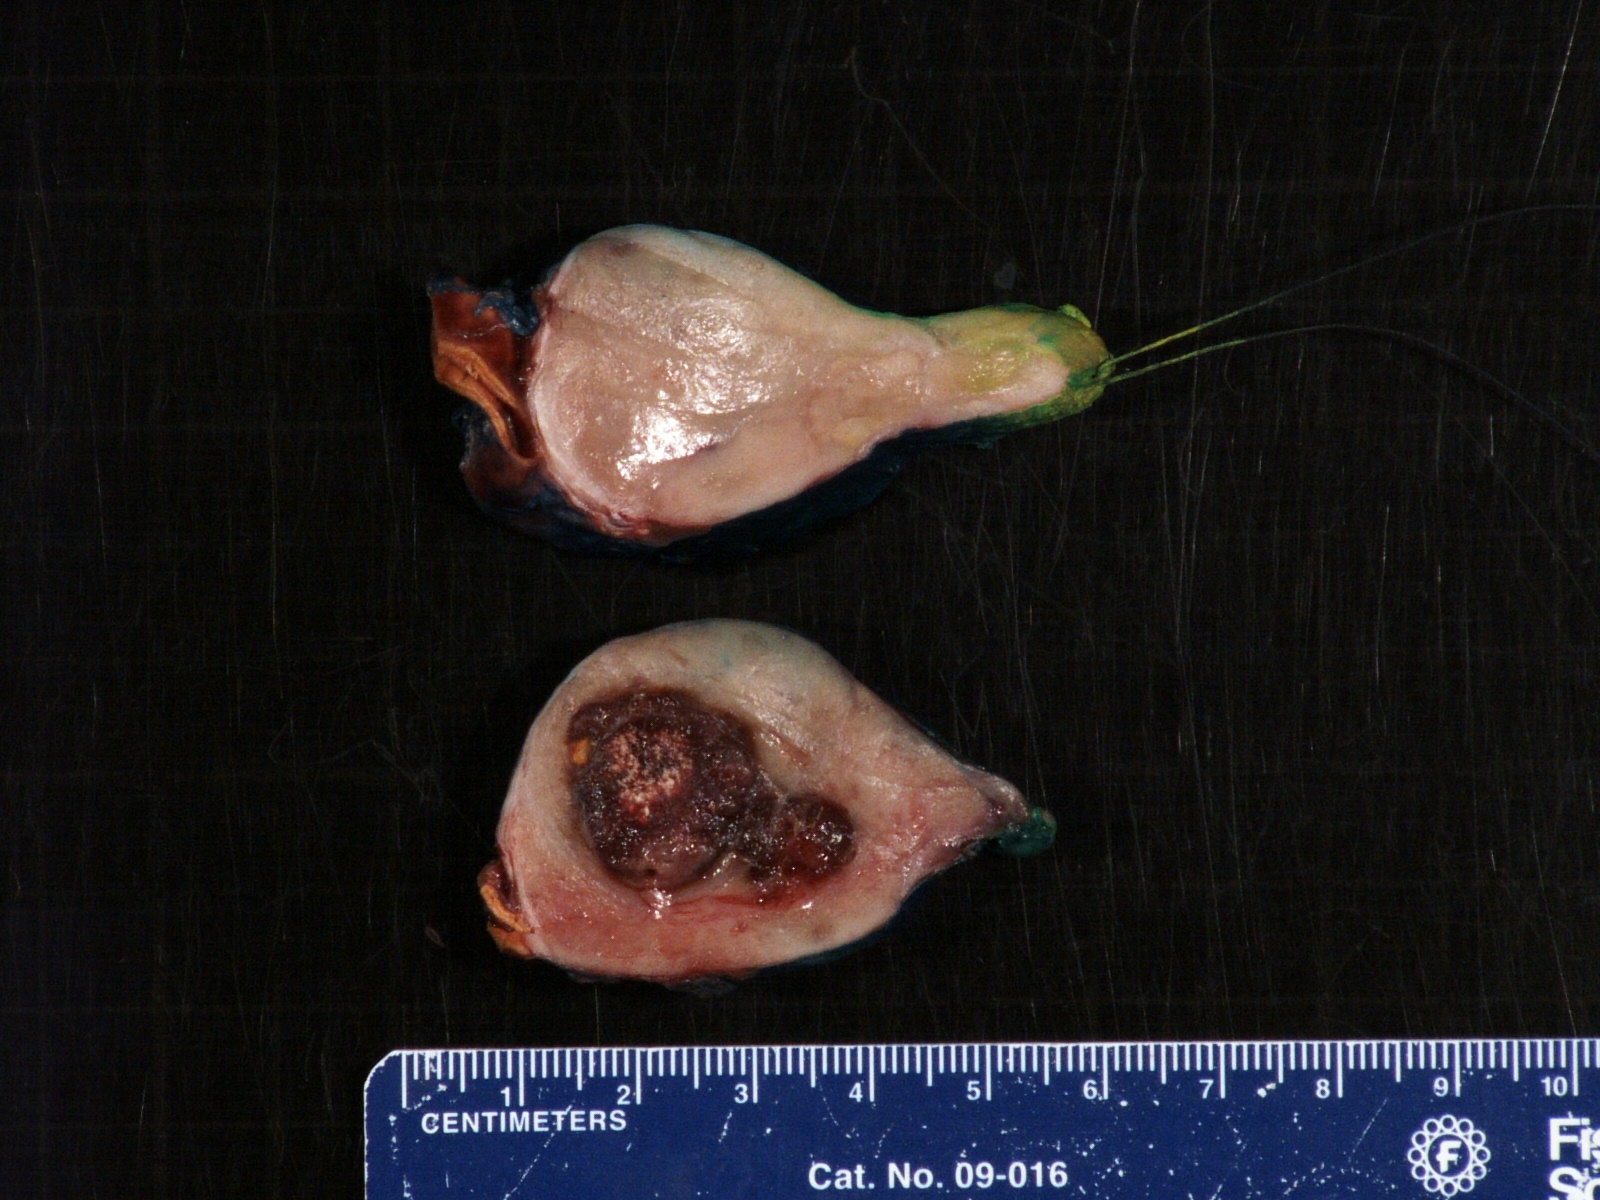

Gross description

- More homogeneous and mature appearance than neuroblastoma

- Varies by subtype, from circumscribed ovoid mass to large multilobulated tumor

- Stroma rich, nodular subtype: area(s) of stroma poor, immature tumor are usually hemorrhagic with well defined borders (J Natl Cancer Inst 1984;73:405)

- Calcification (chalky white, yellow areas) and cystic degeneration may occur

- If large, adrenal gland may be difficult to identify

Gross images